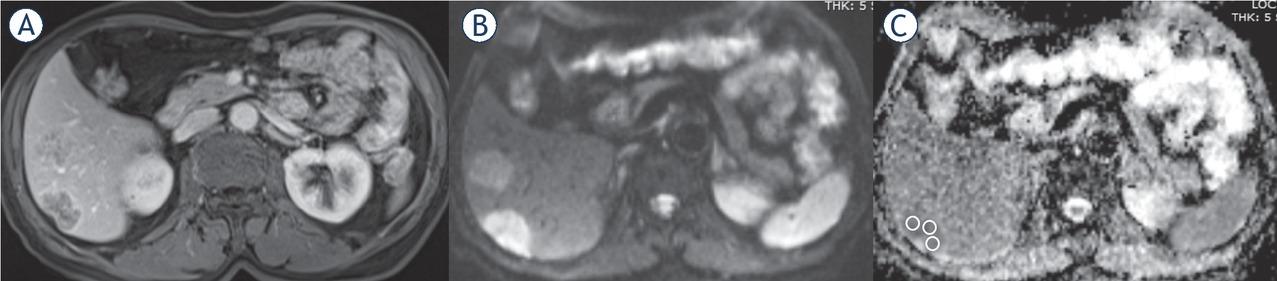

Figure 1

Apparent diffusion coefficient (ADC) values of intrahepatic cholangiocarcinoma (IHCC) and gastrointestinal system (GIS) liver metastases

| Patient Groups | ADC x 10-6mm/sn2 (median, IQR) |

| IHCC | (1293.0), (1422.0–951.75) |

| GIS metastases | (861.0), (1053.0–695.0) |